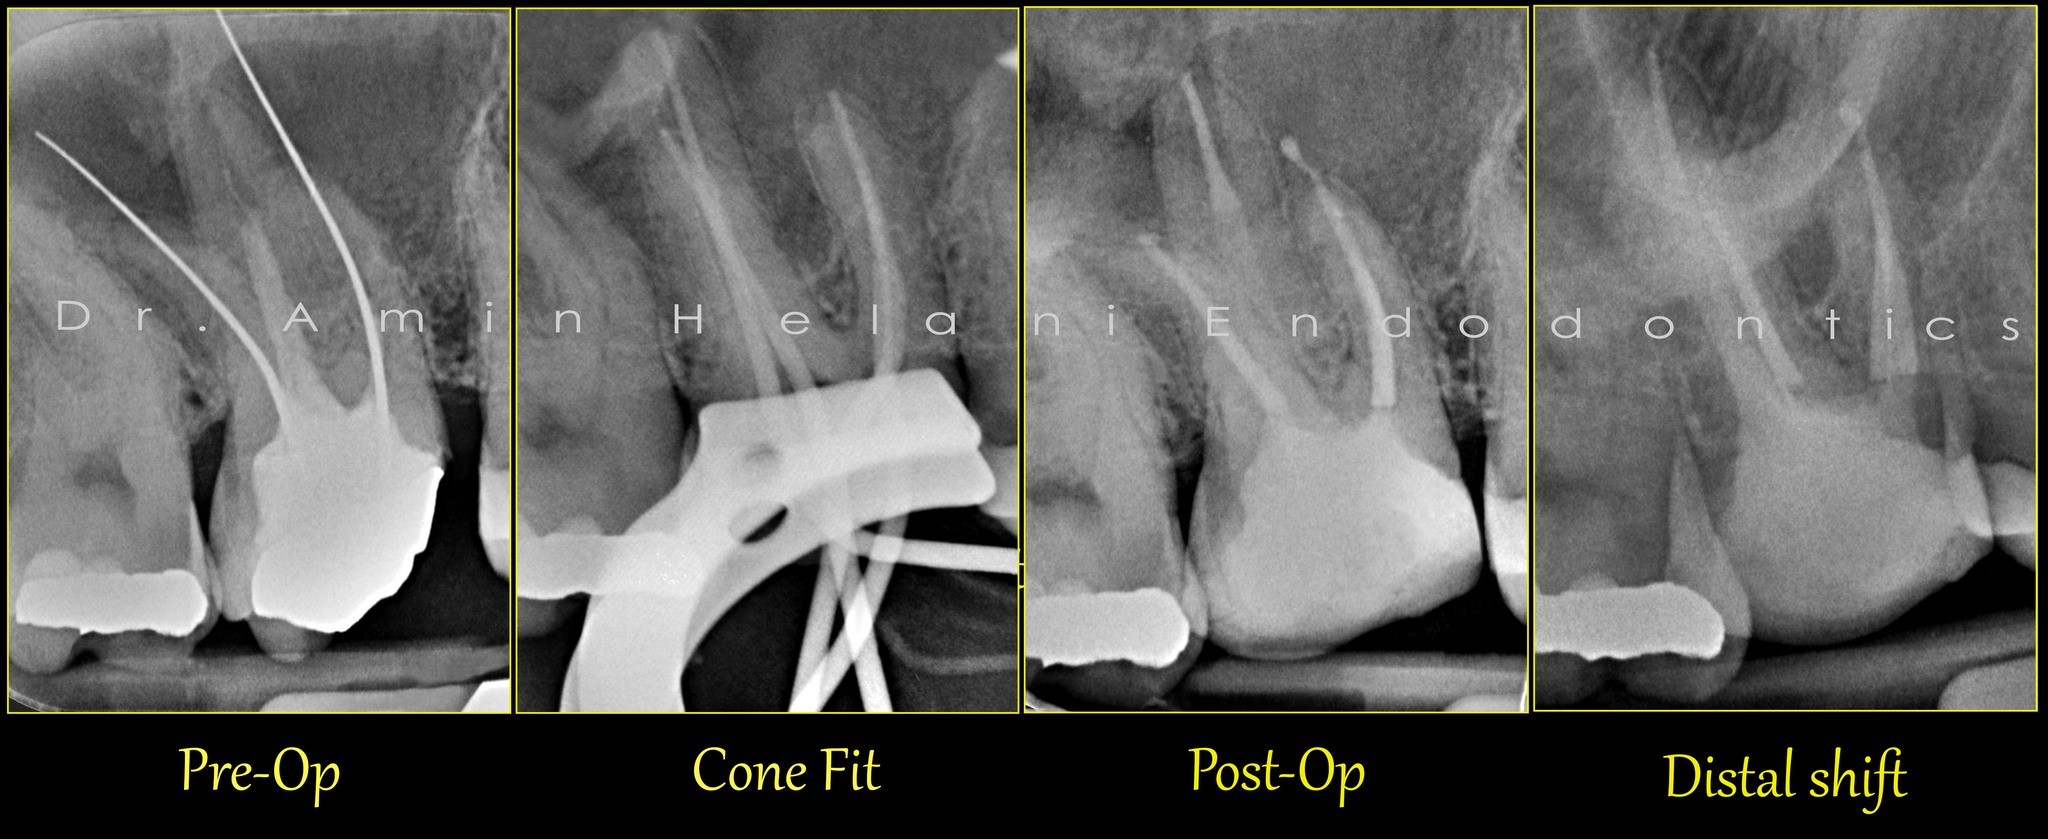

Gekrümmter Kanal im oberen Molaren